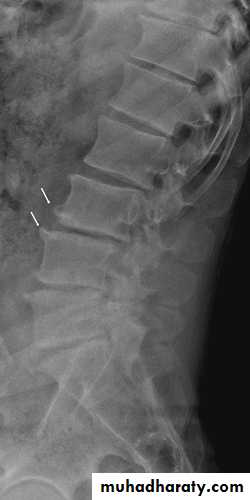

In the Spine :

* Lower cervical and low lumbar spine are most comonly affected.* Osteophytes may encroach on neural foramina (best seen on oblique views).

*Vacuum phenomenon: gas (N2),is pathognomonic of the degenerative process.

* OA of the spine occurs in the apophyseal joints .

Lumbar spondylosis. There is distal narrowing and a vacuum

phenomenon is present in the degenerative discs. Marginal osteophytes arepresent. Inferiorly the facet joints show features of degeneration and, with the increase in lordosis, the spinous processes are in contact

Cervical spondylosis